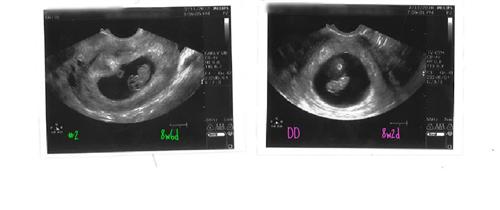

Re: gender at 6 weeks?

Hmmm...very interesting....

With #1(DD) Yolk sac was on the left side at 8w2d

With #2( ) Yolk sac is on the left side at 8w6d

Here is a pic comparison:

|